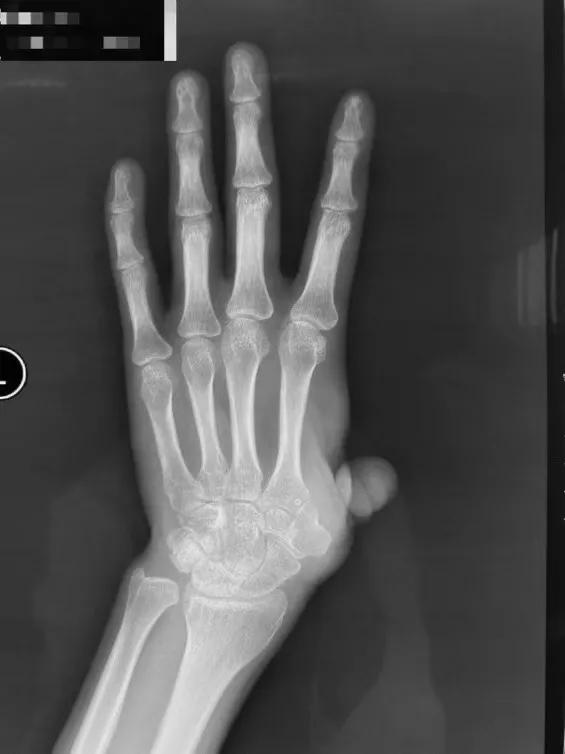

患者因机器伤导致左手拇指在掌骨水平近端离断,在外院进行了再植术,但术后手指存活情况欠佳,随后又做了游离踇甲瓣再造拇指,骨水泥置入等多次手术,但都没有成功保指。目前患者的左手拇指仅残留部分冗余皮肤,无掌骨,外观和功能都受到了极大的影响。

为了保住左手功能,患者慕名来到积水潭医院手外科就诊。陈山林主任检查后发现,他的左手第一系列缺失,若采用传统踇甲瓣结合髂骨移植等办法进行拇指再造,不仅重建的掌骨有被吸收掉的风险,而且患者无法获得有功能的腕掌关节,然而稳定且可活动的腕掌关节恰恰在发挥拇指功能中是最为重要的一环。考虑患者左手仍保留完整的大多角骨,陈山林团队决定为患者定制化制作金属3D打印的第一掌骨,满足患者第一腕掌关节的解剖学重建,为患者的拇指再造提供了一个良好的骨性基础。经文献检索,该技术属于世界首创!

掌骨重建对于患者的拇指再造仅仅是攻克了第一道难关。由于患者拇指反复多次手术,术区皮肤缺损,瘢痕严重,在解决了骨性问题后,下一步的难点则是继续设计皮瓣,解决其皮肤覆盖的难题。对于再造拇指,除了需要进行踇甲瓣游离移植重建拇指指甲,还需要较大面积的足背游离皮瓣进行掌骨处的皮肤覆盖,并同时采用共蒂的第二足趾趾骨游离移植,重建拇指指骨部分。而足部的供区则采用游离腹股沟皮瓣及髂骨进行覆盖,不仅可以保留5个脚趾,而且避免了传统植皮手术给患者带来的不适,同时使供区更加美观。陈山林主任团队术前详细规划,反复推演手术流程,3月5日,在陈山林主任、薛云皓副主任医师、杨辰主治医师、刘畅住院总医师的共同协作下,顺利完成了假体置入,腕掌关节韧带重建,游离穿支嵌合皮瓣移植等复杂精细手术。手术过程非常顺利,术中影像显示,假体位置满意,腕掌关节稳定且具备一定的活动度。再造拇指外观满意,长度合适,各皮瓣存活良好。足部供区外观良好。“手术能够顺利完成,要特别感谢医务部、疾控/院感处、手术室、麻醉科等各个部门对手外科开展新技术给予的全力支持和政策保障。”陈山林主任说。

对于外伤后拇指缺损的患者来说,重建拇指是非常有必要的,拇指功能对于手功能的完成非常重要。常规的拇指再造包括第二足趾游离移植,或是通过髂骨移植重建掌、指骨,再通过踇甲瓣重建拇指指甲和皮肤。也有改良的方式通过踇甲瓣嵌套第二足趾趾骨重建拇指。但不论哪种重建方式,都无法使患者获得具有活动的腕掌关节。而通过定制化的假体制作,即使形状不规则的腕掌关节,也可以达到完美的解剖学重建,使其获得活动。